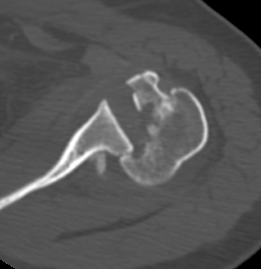

CT scan

Confirms dislocation

Reverse Hill Sachs

Humeral head defect

- caused by impaction of anterior humeral head on posterior glenoid

- intra-articular

- measured as a percentage of the articular surface

Lesser tuberosity fractures

Posterior glenoid fractures / bony bankart